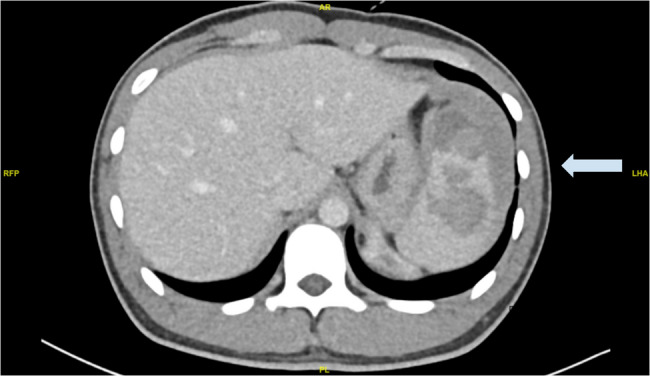

Case presentation: The patient is a 21-year-old male, with no known chronic disease. He is a smoker and complained of a persistent cough for the past three months. He presented the day after a gym session, with sudden left hypochondrium tenderness with no history of trauma, vomiting or diarrhoea. Physical exam revealed normal vital signs and generalized involuntary guarding over the entire abdomen. Initial point-of-care ultrasound was negative for free fluid in the abdomen, but a repeat ultrasound three hours later turned positive. Computed tomography scans of the abdomen, pelvis and mesenteric angiogram were then performed. They revealed intraperitoneal blood, a Grade III splenic haematoma involving the superior pole of the spleen towards the inferior pole, but no active bleeding. The patient was admitted for close monitoring. Initial laboratory evaluation did not show any coagulopathy or infection. The patient remained hemodynamically stable throughout his inpatient stay, and was managed conservatively with rest, analgesia, and empirical antibiotics. Serial haemoglobin levels remained stable, and his symptoms resolved with analgesia. As he remained hemodynamically stable, no repeat imaging was performed inpatient. He was subsequently discharged with instructions to avoid strenuous activities for 4 to 6 weeks. An outpatient follow-up was arranged for him, to review symptoms and monitor haemoglobin level.